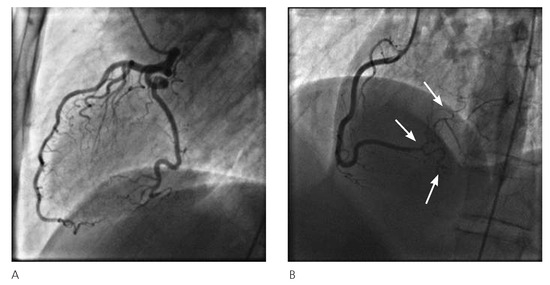

The fact that non-valvular (non-rheumatic) atrial fibrillation creates detectable thrombi in 17% of patients without oral anticoagulation and that 16% of the 17% (over 90% relatively) reside in the left atrial appendage (LAA), suggest that patients w...